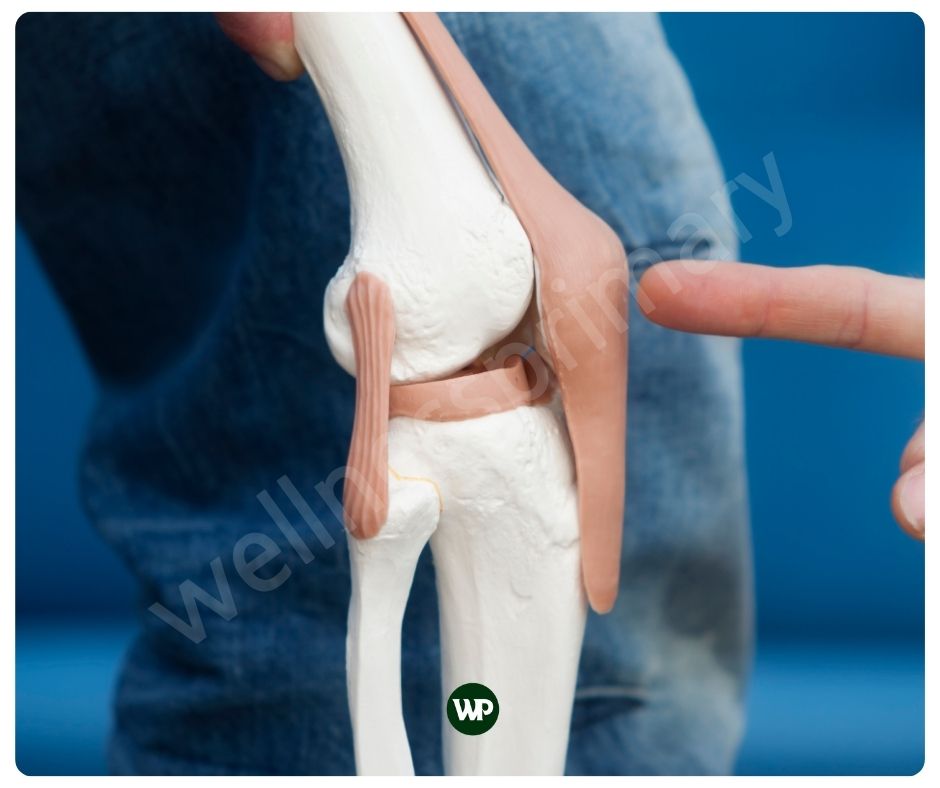

콘드로이친은 연골 조직에 존재하는 물질인데요. 주로 관절과 뼈의 건강에 중요한 역할을 합니다. 콘드로이친은 연골 내에 존재하는 중요한 글리코사미노글리칸의 일종으로, 주로 연골, 뼈, 힘줄, 인대 등에 많이 있습니다. 연골의 주요 구성 요소인 콘드로이친은, 관절의 부드러운 움직임을 도와주며 충격을 흡수해 통증을 완화해 줍니다. 또한 당과 단백질의 복합체인 프로테오글리칸의 일부로, 연골의 탄력성을 높이는데에도 도움이 됩니다. 주로 상어와 소의 연골에서 추출하여 영양제로 섭취할 수 있습니다.

연골은 관절의 움직임을 부드럽게 하고 충격을 흡수하는 역할을 하는데요. 이러한 연골의 역할은 관절이 원활하게 움직이는데 중요하지요. 콘드로이친 효능은 위에서도 언급하였 듯이 연골 조직에 존재하며 연골 내부의 구조를 강화하고 유지하는 데 도움을 주어 관절 건강에 도움을 줍니다. 또한 콘드로이친은 관절의 윤활을 증진시켜, 움직임 시 마찰과 통증을 줄여주어 관절이 부드럽게 움직일 수 있도록 도와줄 수 있습니다.

인간의 연골의 두께는 무릎의 대퇴골 연골의 경우 약 3mm에서 4mm 정도로 가장 두껍습니다. 어깨 관절 연골은 약 1mm~2mm에 불과하지요. 연골은 우리의 움직임을 위해 매우 중요한 역할을 하지만 실제로 매우 얇습니다. 그래서 가능한 빨리 연골 보호에 신경을 써야 합니다. 콘드로이친 효능은 연골의 손상을 예방하며, 이는 특히 연령 증가에 따른 연골 퇴화를 막는 데 중요한 역할을 합니다. 콘드로이친은 이미 손상된 연골의 경우, 그 회복을 돕고, 연골 세포의 재생을 촉진하는 매우 중요한 역할을 합니다.